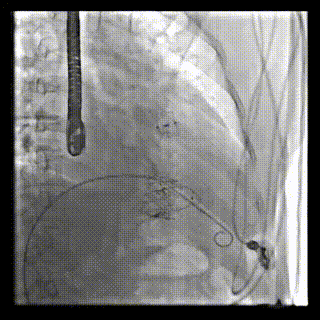

2021年12月24日,復(fù)旦大學(xué)附屬中山醫(yī)院葛均波院士團(tuán)隊(duì)成功應(yīng)用LuX-Valve Plus為一例極重度三尖瓣反流(TR)合并房顫、房缺的患者完成了經(jīng)血管三尖瓣置換術(shù),這是在前基礎(chǔ)上,本周完成的第三例經(jīng)血管三尖瓣置換手術(shù),葛均波院士、周達(dá)新教授等與心外科魏來(lái)教授、賴顥教授,心超室的潘翠珍教授、李偉教授及麻醉科的郭克芳教授共同完成了本周手術(shù),均獲得圓滿成功!患者術(shù)后超聲顯示無(wú)TR,臨床癥狀明顯改善。本周手術(shù)的成功也為L(zhǎng)uX-Valve Plus救治性臨床研究添上了濃墨重彩的一筆。

三例患者入院后,葛均波院士團(tuán)隊(duì)周達(dá)新教授、潘文志教授、張?jiān)床┦?、陳莎莎博士及心超室的潘翠珍教授、李偉教?/strong>對(duì)患者的情況進(jìn)行詳細(xì)評(píng)估和討論,最終決定為三例患者選擇LuX-Valve Plus40mm、50mm和50mm型號(hào)的瓣膜進(jìn)行手術(shù)治療。手術(shù)后即刻拔除氣管插管,術(shù)后患者三尖瓣反流癥狀得到顯著改善,復(fù)查心超結(jié)果顯示人工三尖瓣瓣膜支架固定穩(wěn)定,瓣葉關(guān)閉形態(tài)未見(jiàn)異常,未見(jiàn)明顯反流。

LuX-Valve Plus是LuX-Valve系列產(chǎn)品的第二代,采用的是經(jīng)血管入路的全新輸送系統(tǒng),其設(shè)計(jì)開發(fā)過(guò)程得到了上海中山醫(yī)院葛均波院士及其團(tuán)隊(duì)的精心指導(dǎo),研究結(jié)果提示瓣膜植入的安全性和有效性俱佳,尤其瓣膜獨(dú)特的設(shè)計(jì)使其具有極佳自適應(yīng)性,本周三例患者病因及解剖結(jié)構(gòu)各具特點(diǎn),但均可從LuX-Valve Plus植入術(shù)明顯獲益。目前,LuX-Valve Plus已在全國(guó)各中心開展救治性臨床研究,相信未來(lái)定會(huì)為更多的三尖瓣反流患者帶來(lái)福音。